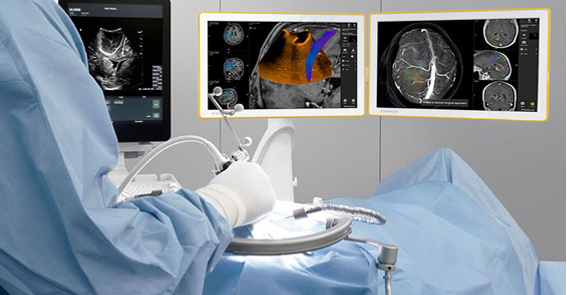

O equipamento fornece uma melhor orientação para ajudar a direcionar, com precisão, as lesões identificadas nas imagens da RM. Esta função permite a redução potencial do risco de perda de tumores de alto grau ou subestimados para vigilância ativa. O bkFusion assegura que as imagens de ultrassom em tempo real e os alvos da RM permaneçam alinhados, quer na abordagem transretal à mão livre ou na biópsia transperineal.

O urologista pode ajustar livremente o ganho e a profundidade ou optar por uma varredura em diferentes planos (transverso, sagital e “endfire”), sem necessidade de recalibração, antes ou durante os procedimentos. Isto auxilia no melhor direcionamento das áreas de preocupação.

Os dados da ressonância magnética e o relatório radiológico são analisados pelo médico. O profissional faz o contorno da próstata e das lesões suspeitas para posteriormente carregar estes dados no sistema.

O passo seguinte consiste em biopsiar as lesões, que de acordo com o planejamento prévio, podem ser iniciadas pelas biópsias alvo, e depois para as biópsias sistemáticas. Na técnica transperineal, o sistema atua em conjunto com o stepper, para fixar o transdutor, mantendo seu posicionamento e deixando as mãos do médico liberadas para operar a agulha desse procedimento. Além disso, o stepper é eletronicamente conectado ao equipamento de ultrassom.

Durante o procedimento, o urologista também pode, graças à capacidade da Fusão Preditiva, readaptar e reorientar a posição supina da RM para coincidir com a orientação da biópsia da próstata em tempo real. A função permite que o médico não fique “amarrado” a um modelo na tela que não pode ser reajustado, representando um grande benefício.

A principal característica do bkFusion é a possiblidade de realizar procedimentos de biópsia transretal (TR) e transperineal (TP) em um sistema integrado. O grande ganho para os usuários é o fluxo de trabalho virtual.